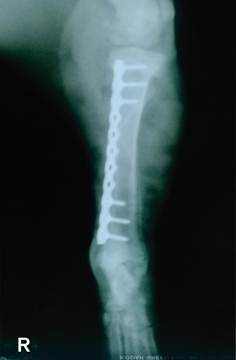

Se resolvió sin complicación intraoperatoria, en las radiografías posoperatorias inmediatas se observaron el implante en su posición (Figura 5 y 6), se recomendó realizar placas de rayos X de control a 20 y 40 días después de la cirugía hasta evidenciar radiográficamente la unión ósea, por otro lado, se indicó a los propietarios sobre caminatas reducidas y un espacio regular durante las primeras 2 semanas de intervención quirúrgica. El tratamiento antibiótico, antinflamatorio posoperatorio de administración Ketoprofeno (2 mg/kg iv, c/24 h), Tramadol por vía oral (2 mg/kg c/8 h) para manejo del dolor, Cefalexina (20 mg/kg im, c/12 h) para evitar infecciones secundarias por 3 días.

Figura 5 alineaciones en el plano sagital en la proyección mediolateral, placa bloqueada de holes de 9 mm y tornillos de bloqueo de 3.2 mmx12 mm, 8 mm

En nuestro caso se observó esta limitación a pesar de ser una técnica OPMI existe un espacio de 3 mm aproximadamente detalle que se muestra en la (Figura 5) mediciones de aproximación entre los segmentos de fractura que se pudo obtener con las placas radiográficas de tamaño real.